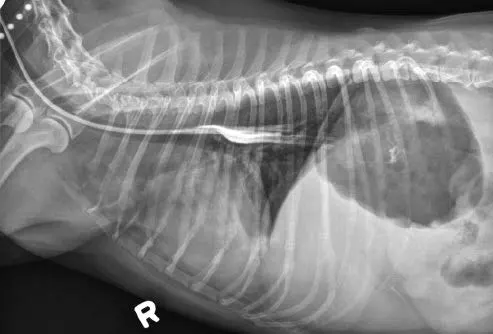

Tubes can be accidentally misplaced in the trachea (Figure 2A), nasopharynx, or nasal cavity, and subsequent feeding may result in aspiration pneumonia; therefore, appropriate placement should be confirmed before feeding is initiated. Various inexpensive methods can help verify tube location: laryngoscopic visualization of the tube entering the esophagus; suction to verify negative pressure; air infusion while auscultating the abdomen for borborygmus; infusion of sterile saline or nonionic contrast medium (Figure 2B), which sometimes elicits a cough with tracheal placement; or pH assessment of fluid aspirated from the tube.

Inadvertent placement of an NG tube in the trachea and bronchus of a miniature dachshund (11 years of age). This dog had a severe pulmonary interstitial pattern secondary to infusion of 20 mL of sterile saline through the tube; it had no cough reflex during infusion (A). After injection of 3 mL of iohexol 240, positive contrast medium outlined the alveoli, particularly in the caudodorsal thorax, confirming tube misplacement (B). The following day, radiography confirmed that contrast medium and saline had been cleared from the lungs.

Verify tube location with survey (A) or contrast (B) radiography. Inject 2–3 mL of iohexol or other nonionic, iodinated contrast medium into the tube, followed by 3–5 mL of air or sterile saline. Note how the contrast medium highlights the esophageal folds.

Author Insight

When an NE tube is placed appropriately, its end is located at the eighth intercostal space (approximately). Even properly placed tubes can appear to be in the airways, because the esophagus overlies the trachea and bronchi on caudal cervical and thoracic radiographs.

In this dog, the proximal end of the tube is not associated with the trachea.